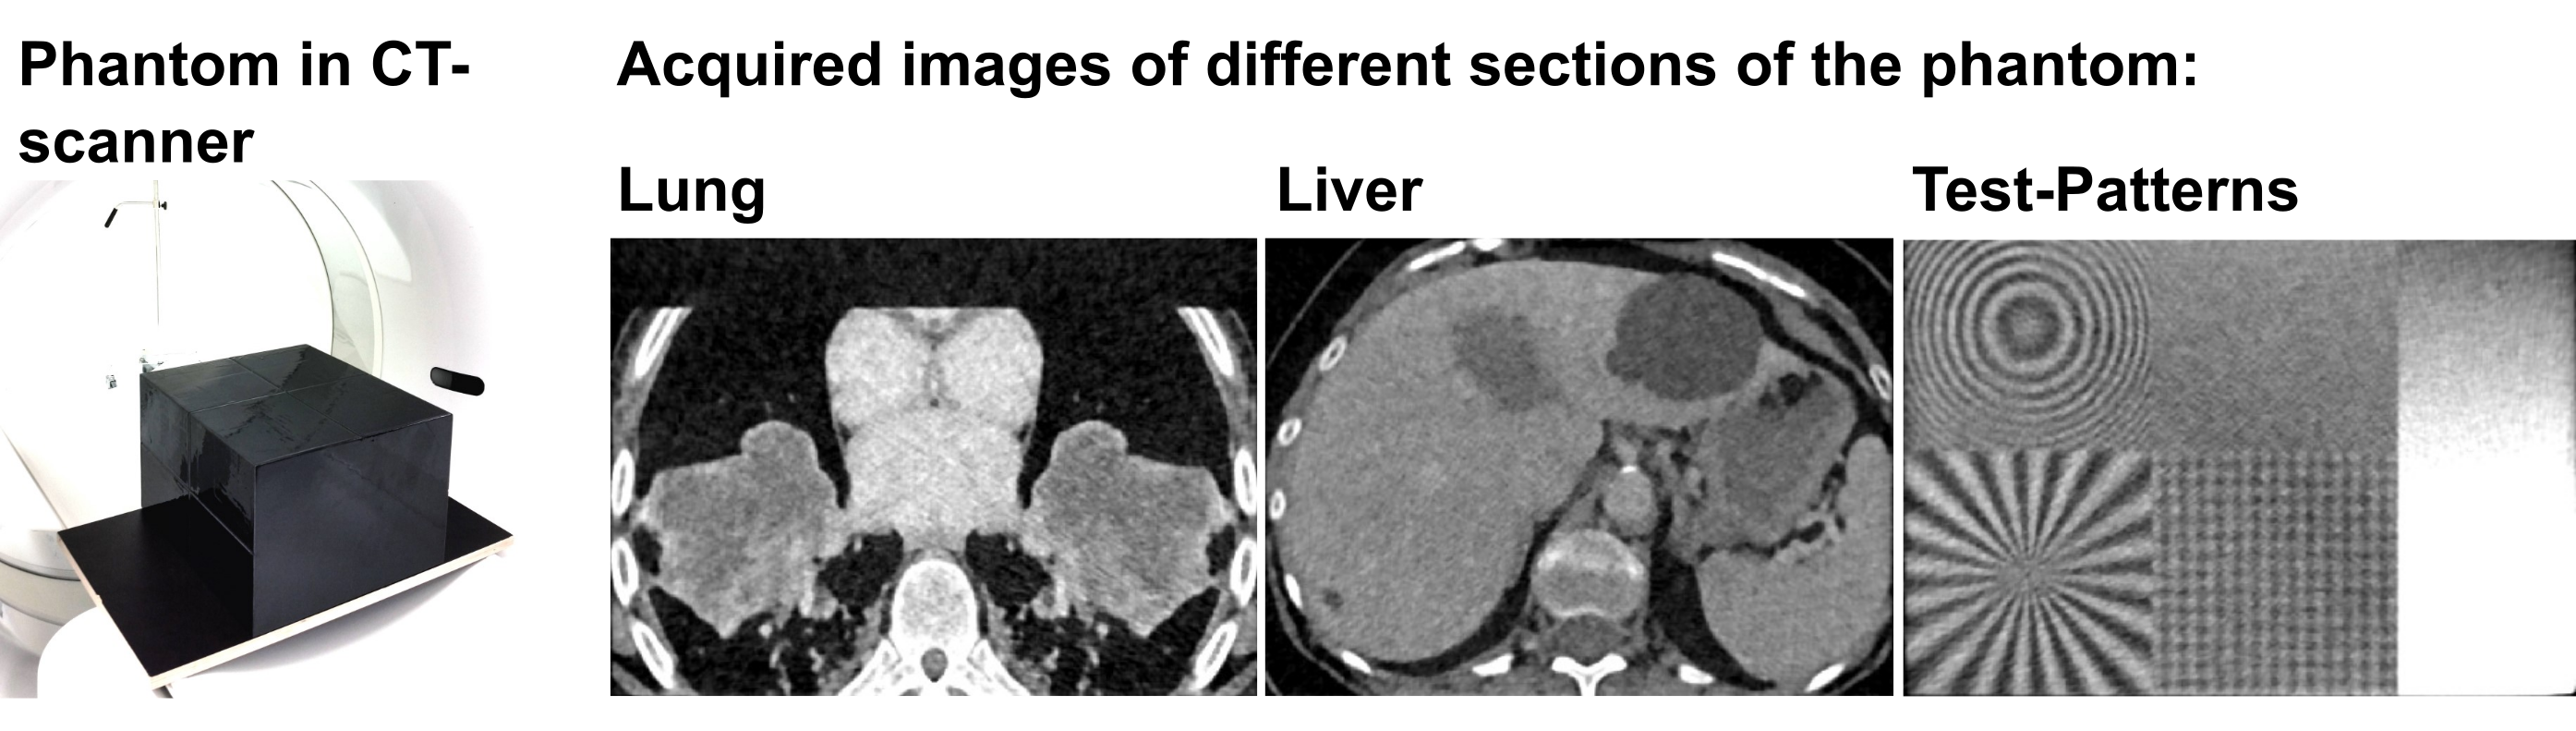

Standardized CT Multicenter Dataset

The dataset contains highly anthropomorphic CT phantom images from the thorax, the abdomen, and test patterns (see figure 3). The datasets were acquired in a standardized manner at 8 institutions (5 University Hospitals and 3 other imaging centers) and in total at 13 CT machines. All common vendors are represented (Siemens, Philips, Canon/Toshiba, GE). The dataset can be used, for example, to compare biomarkers or quantify their expected variations. This helps in the design of clinical trials and the development of new biomarkers that potentially are used in the future at several stages of patient care: for diagnosis, staging, and prognosis, as well as for predicting and detecting treatment response.

Figure 3: CT Phantom and its different sections after image acquisition.